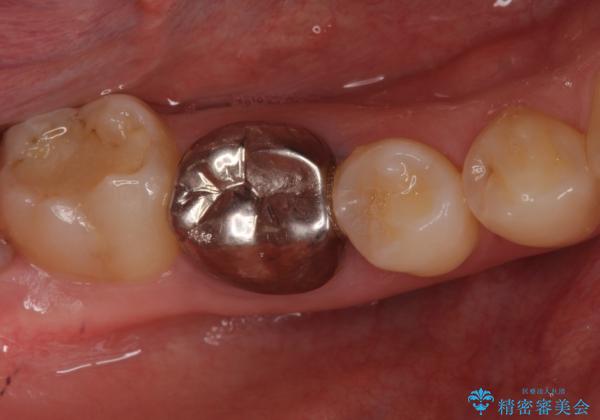

- 右下の奥歯に入れた銀歯を白くしたいとのことで来院されました。

根っこの治療がされていますが、症状もなくレントゲン画像で病変も確認できないため根管内には触れず被せ物のやり替えのみとなりました。

下の奥歯は口を開くと簡単に外から見えてしまいます。

銀色だった歯が白くなったことで大変喜んでいただけました。